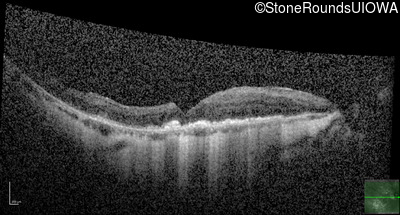

This 81 year old man began using a flashlight to read menus in his 40's. At age 75 his ophthalmologist noticed abnormal fundus findings and referred him to a retina specialist.

Diagnosis & molecular findings

| Late Onset Retinal Dystrophy | C1QTNF5 | Ser163Arg AGC>AGA | AD |

Disease:

Gene:

Allele 1:

Ser163Arg AGC>AGA

Inheritance:

AD